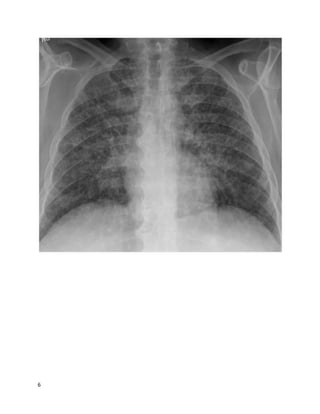

You receive an email from a colleague asking for a "curbsideconsult." You haven't

heard the story or your colleague's question yet, but to frame your thinking, you

quickly glance at the images she's attached to the email.

6

7

8

Based on these images, what's the most likely clinical scenario?

We feelthat A is the best answer.

The chest X-ray shows reticulonodular opacities, a nonspecific abnormal finding.

The axial CT cuts show:

 Small nodules in a lymphangitic pattern, i.e., touching the pleura/fissures

 Pleural effusions with an irregular, nodular contour

9

 Irregular thickening of the interlobular septa

 Peribronchovascular thickening

All these findings are consistent with this patient's diagnosis of lymphangitic

carcinomatosis(LC): diffuse metastatic spread of cancer to the lungs, where it

diffusely infiltrates and obstructs lymphatic channels. 80% of cases are due to

adenocarcinomas, most often from a primary cancer of the breast, lung, or colon.

This case of LC was from a primary pancreatic adenocarcinoma.

Chest films are usually normal in lymphangitic carcinomatosis.